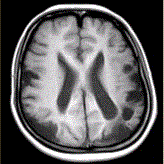

问题 女性,22岁。癫痫发作及智力异常。MRI显示见下图。 关于该病描述正确的是

选项 A.脑萎缩 B.双侧顶枕叶软化灶 C.蛛网膜囊肿 D.双侧顶枕叶脑梗死 E.脑积水 F.脑炎

答案 AB